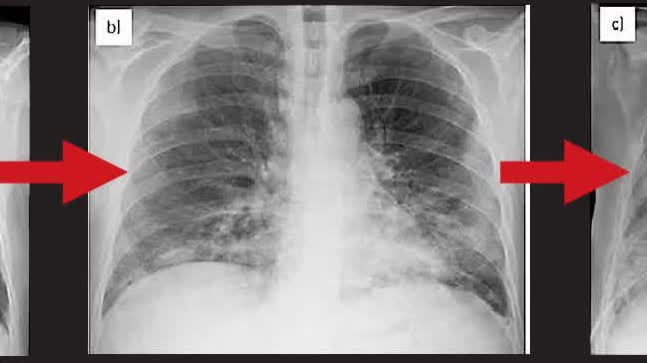

據悉這些在歐洲國家流行的肺炎病症相對較為溫和,患者的肺部在X光片會呈現白色。丹麥血清研究所警告說,預計這種肺炎的病例會在冬天持續增加。